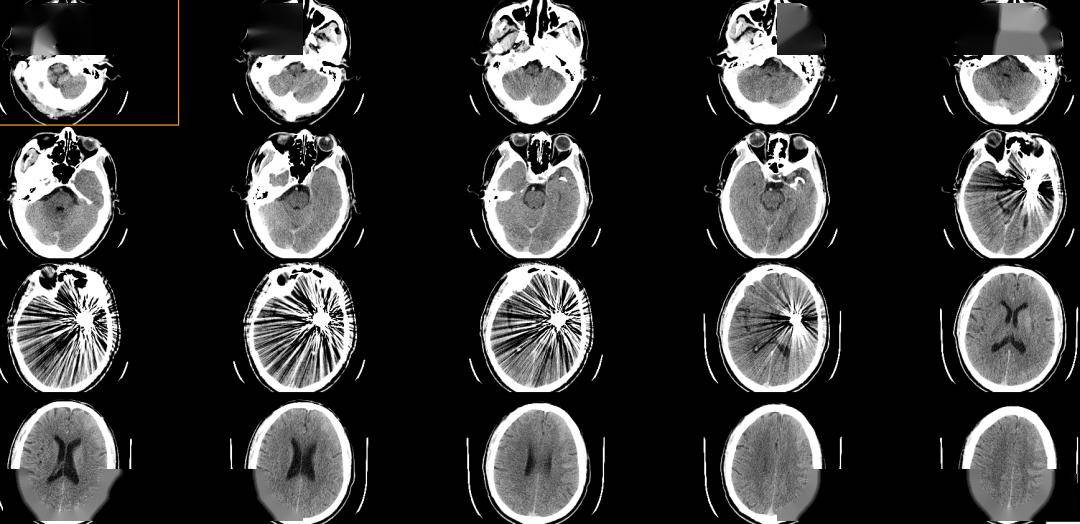

术前影像

术前正位DSA

术前侧位DSA

术前核磁

初步诊断:左侧大脑中动脉M1段动脉瘤

侧别、位置:左侧

动脉瘤的形态:囊性

动脉瘤大小:长24.8mm、宽23.1mm、高20mm

动脉瘤颈宽度:6.2mm

载瘤动脉直径:远端3.1mm,近端3.9mm